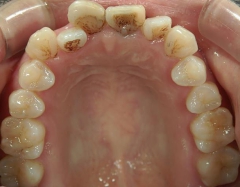

矯正歯科 治療前矯正歯科 治療前

矯正_灰色.pngno.37_7548_治療前_上.JPG矯正_灰色.png